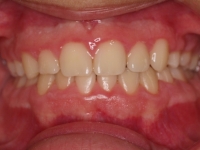

La paciente O.O. acude a nuestra consulta por:

– Canino 13 e incisivo lateral 42 en posición ectópica.

– Canino 23 incluido.

Con lo que decide realizarse un tratamiento de ortodoncia de duración de 24 meses con brackets damon Q.

CASO COMPLETO: